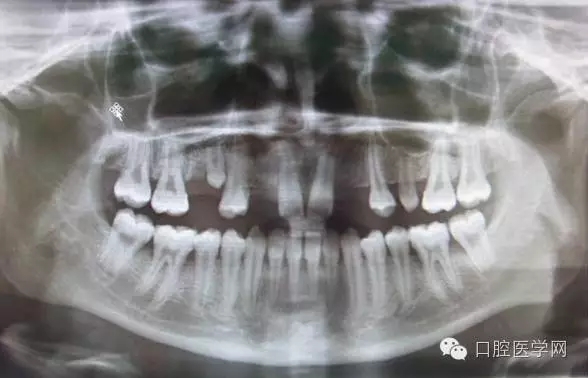

3.牙齒數(shù)目異常

額外牙

X線表現(xiàn):最多見于上頜兩中切牙之間;圓錐形,根短小;拍攝X線片可確定額外牙的數(shù)目、位置、形態(tài)與鄰牙的關(guān)系。